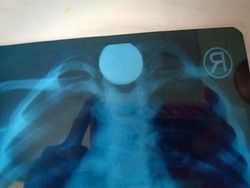

Mengeluh Sakit Perut, Ternyata Ada Beragam Perkakas Ditemukan di Lambung

Seorang pria di India datang dengan keluhan sakit perut yang tak tertahankan. Hasil pemeriksaan menunjukkan ada beragam perkakas bersarang di dalam perutnya.